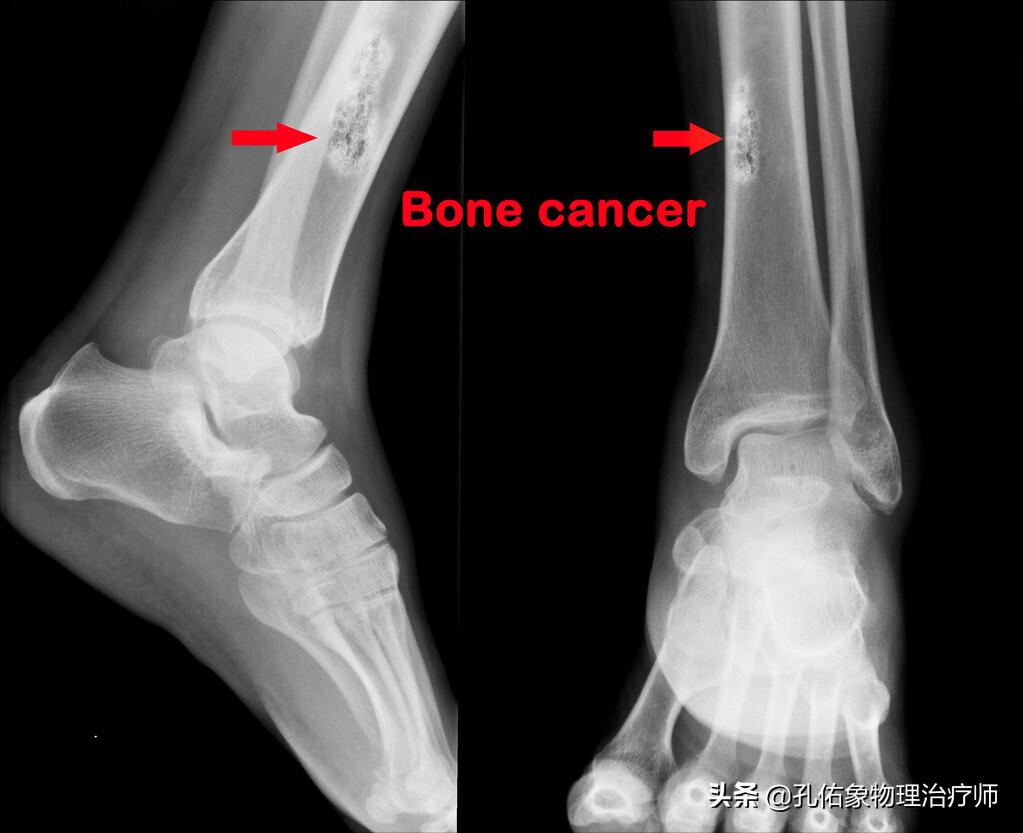

1.恶心肿瘤骨转移

特别是一些癌症中期的人,比如肝癌、肺癌、甲癌、癌骨转移等,在早期的时候表现出倦怠、无力、食欲减退、体重减轻,逐渐会表现出各种疼痛,夜间肢体抽搐、抽筋。